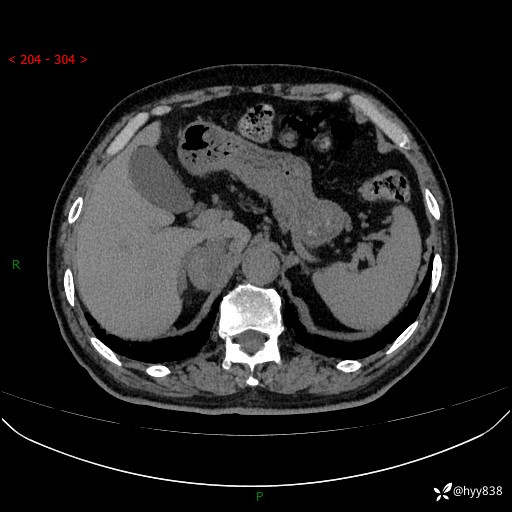

【患者信息】:76岁/男

【主诉】:检查发现右侧肾上腺占位6天

【现病史及既往史】:患者6天前体检发现右侧肾上腺占位,无腰痛,无放射痛,无尿频、尿急、尿痛及肉眼血尿,无畏寒、发热,无恶心、呕吐,今为求进一步治疗,遂来我院就诊,门诊拟“右侧肾上腺占位”收住入院。 起病以来,患者精神、饮食、睡眠可,大小便如常,体力体重无明显变化。

【检查】:肾上腺CT平扫+增强